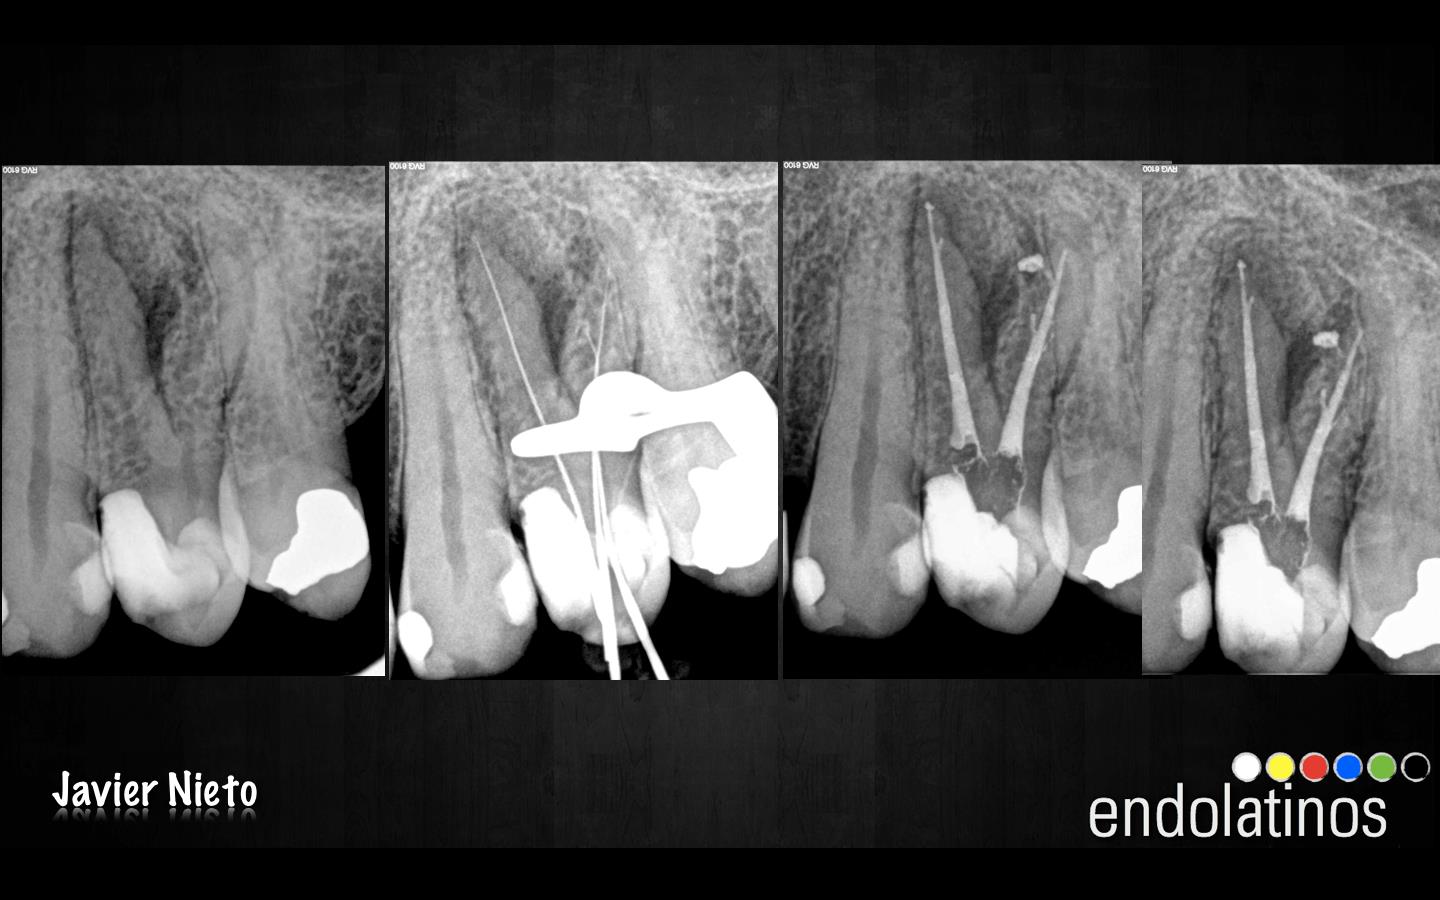

Se trata de un paciente joven, 25 años de edad, diagnosticado con una pulpitis irreversible, se instrumentaron los conductos con el sistema de limas rotatorias de Ni-Ti , Mtwo, hasta un 25-6%. Procuramos hacer hincapié en la fase de irrigación, ya que conformamos el conducto bastante rápido, por tratarse de sistemas de conductos amplios, y sospechabamos de itsmos mesiales en su anatomía, con lo que debíamos eliminar el tejido pulpar. Usamos hipoclorito al 5% activandolo después de haber irrigado con EDTA para eliminar la capa de barrillo dentinario. Se activó con las Irrisafe, y después dejamos actuar al hipoclorito durante dos fases de 3 minutos. Se obturó con condensación vertical con la técnica de Ola continua de Buchanan algo modificada, creando más masa de gutapercha en la parte del tercio medio y apical. Un backfilling con una técnica de gutapercha inyectada con la pistola Obtura III.

Estaríamos ante un caso tratado de la misma manera que el anterior, este paciente también sería joven, de unos 28 años de edad, con una pulpitis irreversible, como vemos también presentan itsmos entre los conductos de la raíz MesioVestibular.

Este último caso, se trata de una necrosis de una pieza 2.4 con gran lesión apical. Lo publiqué por el motivo que a veces, localizamos unos conductos laterales o accesorios y lo complicado que nos resulta el saber si lo hemos obturado completamente. Siempre nos queda esa duda, son los límites que nos encontramos en un tratamiento por vía ortógrada, no podemos pretender manejar todas las situaciones de manera perfecta. Aunque este caso, en el que buscamos el éxito con la regeneración y curación de la lesión, nuestra finalidad es la perfección, obviamente imposible.